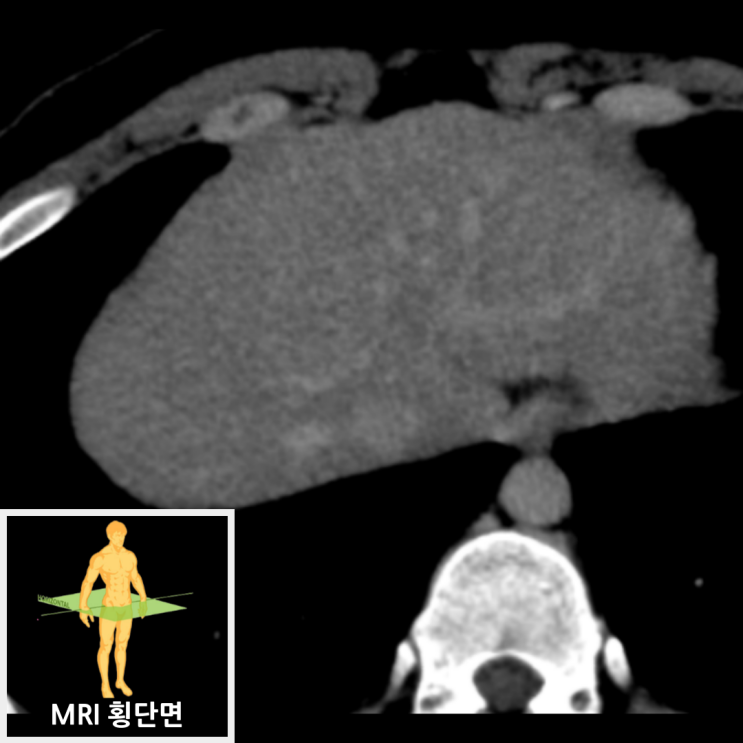

복부CT에서 중간 간엽에 3cm크기의 고음영 결절이 보였으며, 이 결절은 지연기 영상에서 간 실질과 동음영을 보였습니다. 추가적 확인을 위해 MRI를 촬영한 결과, CT상 결절은 MRI 20분 지연 영상에서 간 실질보다 고신호로 보이고 있으며, 가운데에 섬유증 반흔이 보여 국소결절과형성으로 판단되었습니다.

• 복부MRI 20분 지연 영상: 국소결절과형성 확인 복부MRI 20분 지연 영상: 국소결절과형성 확인